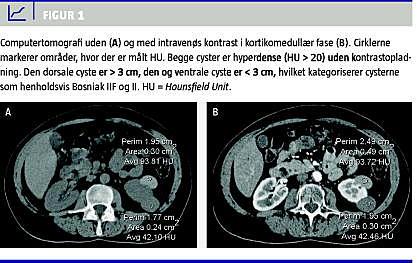

I denne kategori er der tale om mere komplekse cyster, som ikke kan klassificeres som kategori II- eller III-forandringer (Figur 1 ). De er potentielt maligne og skal følges (F = followup) med kontrol-CT. Kontrol-CT skal afgøre, om de cystiske forandringer er uforandrede i kontrolperioden og dermed tolkes som benigne, eller om de ændrer morfologi og/eller kontrastopladningsmønster, som medfører, at de opgraderes til kategori III. Der foreligger ingen publicerede data om, hvor længe patienterne bør følges. M. A. Bosniak anbefaler selv første kontrol efter et halvt år. Hvis læsionen forbliver uændret, fortsættes med kontrol-CT en gang årligt i minimum fem år [24]. Andre anbefaler tæt opfølgning i et år med CT efter tre, seks og 12 måneder [10]. Patienter med komplekse Bosniak IIF-cyster bliver på vores afdeling fulgt efter sidstnævnte skabelon og i tilfælde uden progression herefter en gang årligt i fem år. Man skal imidlertid være opmærksom på, at meget tætte kontroller kan svække detektionen, hvis ændringen fra gang til gang kun er meget lille.